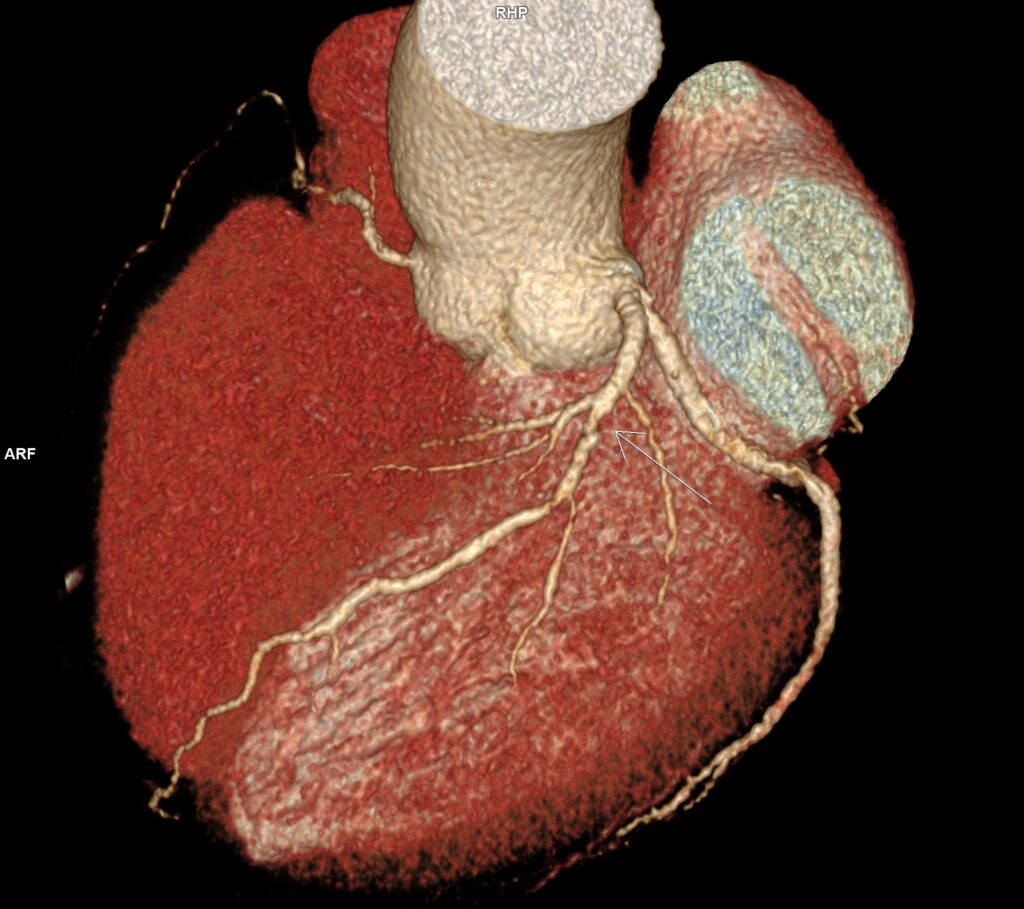

Figura 3: reconstrucție volumică (VRT) din examinarea inițială cu evidențierea stenozei severe de la nivelul arterei descendente anterioare

Figura 8: reconstrucție volumică (VRT) din examinarea inițială cu evidențierea stenozei severe de la nivelul arterei circumflexe

Discuţie caz nr 114: Examinarea cardioCT are indicație de clasa 1 la pacienții cu sindroame coronariene cronice; la acest pacient se poate observă evoluția în dinamică a unor plăci de la nivelul arterei descendente anterioare – indicația de repetare a investigației s-a datorat faptului că pacientul acuză dureri de tip anginos nou apărute la 5 luni după coronarografia cu implantare de stent pe arteră circumflexă.

DE LUAT ACASĂ!!! Examinarea cardioCT este indicată la pacienții cu sindroame coronariene cronice datorită valorii predictive negative mari, are tendința de a supraestima gradul de stenoză mai ales când este și calciu în placă și este urmată de coronarografia invazivă pentru diagnostic și, eventual, tratament în cazul în care se decelează stenoze severe (reducere de lumen mai mare de 70%).